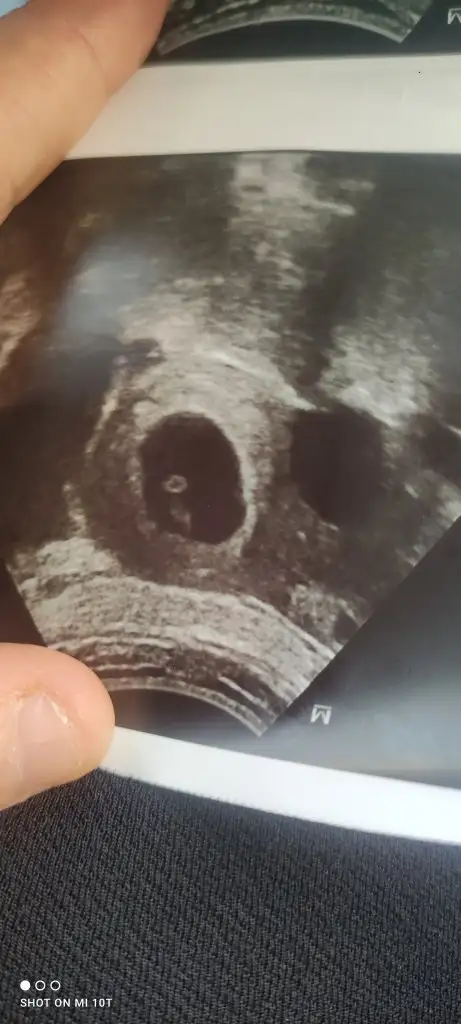

Bnm şuan 11+3 haftalık gebeyim üç kızım var hepsi sol taraftaydı bu hep sağda ve geçen doktor a gittim çıkıntı var erkeğe benziyor dedi net bir şey söylemedi bunda çok mide kazıntım var yemek ler den nefret ediyorum artık jiç görmek bile istemiyorum bu çok farklı ama içimde bir umut inşallah oğlum olucak doktor erkeğe benziyor dedi çıkıntı var dedi kızlarda hiçbir doktor böyle söylemedi inşallah sağlıklı bir oğlum olur ama kız solda erkek sağda ve kızlar da karın daha yukarıda ve geniş yuvarlak olur erkek şerde daha sivri aşşağı da olur bnm karnım çok erken çıktı neden bilmiyorum bana dua edin Allah ım erkek evlat sevgisi ni tattırsın inşallah